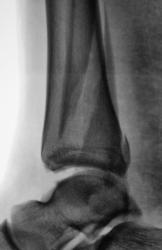

Пол пациента: Мужской пол Тип патологии: Травма Область исследования: Скелетно-мышечная система Методы исследования: Rg Пациенту в ургентном порядке был произведен "первичный снимок". Сегодня пациента доставили на "контрольный снимок". Какие мнения будут уважаемые коллеги? 1.REp_..jpg 2.REp_..jpg 3.REp_..jpg 4.REp_.jpg ВложениеРазмер 1.REp_..jpg70.64 КБ 2.REp_..jpg90.44 КБ 3.REp_..jpg84.75 КБ 4.REp_.jpg72.61 КБ Ср, 09/12/2009 - 20:21 #1 Иринка Не на сайте Был на сайте: 11 лет 5 месяцев назад Зарегистрирован: 16.11.2009 - 22:14 Публикации: 190 Трёхлодыжечный перелом с разрывом дистального межберцового синдесмоза и подвывихом стопы кнаружи. Репозиция неудовлетворительная, показано оперативное лечение. Ср, 09/12/2009 - 20:25 #2 v1tal Не на сайте Был на сайте: 4 года 9 месяцев назад Зарегистрирован: 07.06.2008 - 19:41 Публикации: 1779 На оперативное разрешение все "бонусы" собраны. "Знаешь, у некоторых врачей есть комплекс мессии — им необходимо спасать мир. А у тебя комплекс Рубика — тебе необходимо решать головоломки."

Трёхлодыжечный перелом с разрывом дистального межберцового синдесмоза и подвывихом стопы кнаружи. Репозиция неудовлетворительная, показано оперативное лечение.